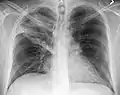

| A chest X-ray showing a very prominent wedge-shape bacterial pneumonia in the right lung | |